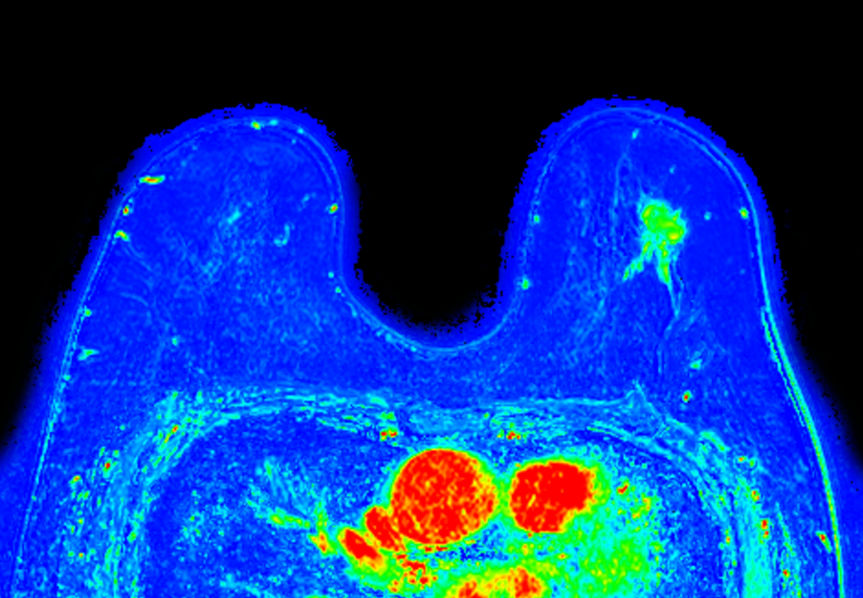

Dynamic 3D mDIXON XD (washin) Compressed SENSE